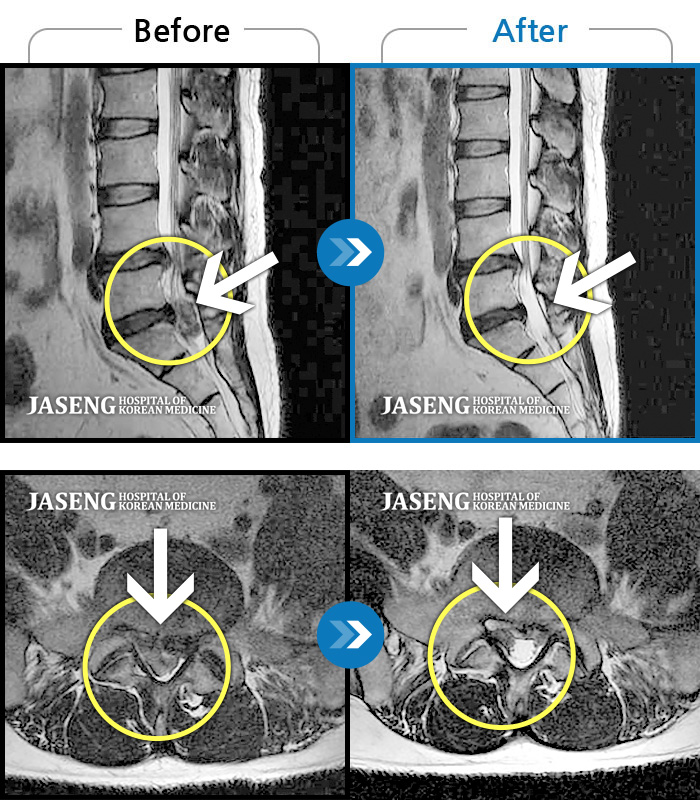

허리디스크

잠실 · 한상욱 원장

우측 엉치부터 우측 다리부터 발끝까지 저리고 아프다. 감각까지 먹먹하다.

촬영시기

2022.04.15 ~ 2022.10.22

2022.12.02

조회수 121